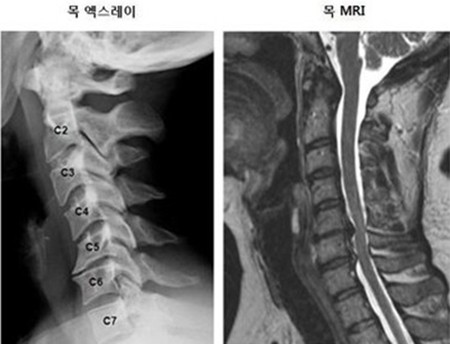

척추에는 뼈의 정렬과 움직임 그리고 안정감을 담당하기 위함으로 지지대 역할을 하는 여러 인대가 존재해요. 전형적으로 척추 전방의 전종인대와 후방의 후종인대를 들 수 있어요. 척추는 목 부위의 경추부터 꼬리뼈 주위 천추에 이르는 33개의 뼈로 되어 있으며 척추관은 척추 가운데 관 형상의 빈 공간으로 척추관 속에는 뇌로부터 팔다리까지 신경이 지나가는 통로라고 할수 있습니다.